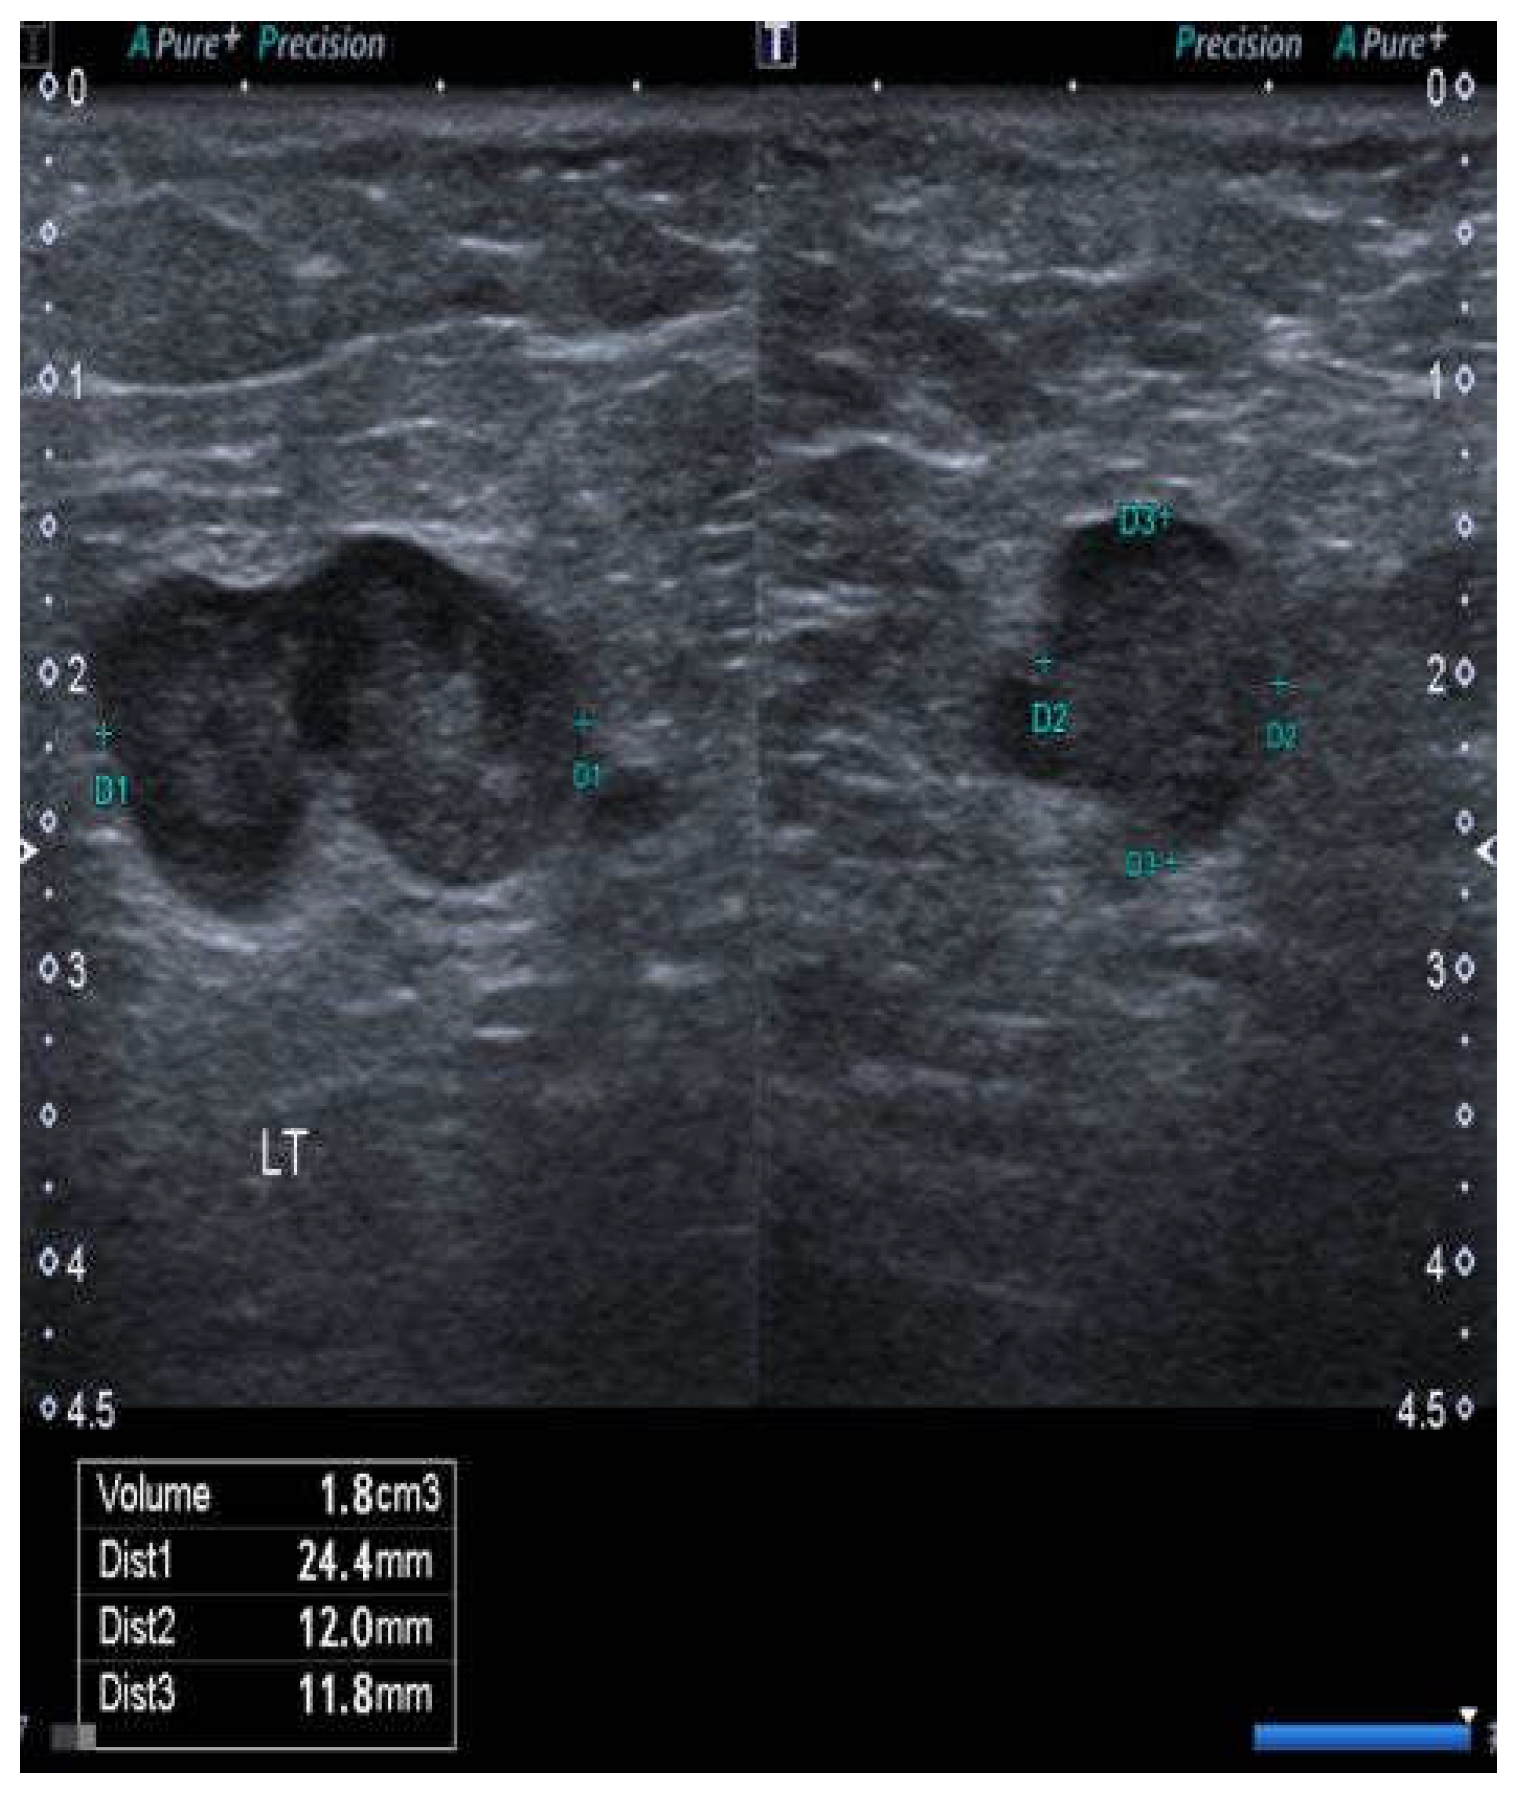

Lymph nodes were considered suspicious if there was generalized or focal cortical thickening, any inhomogeneity of the texture of either the cortex or medulla, the absence of the medulla or hilum, focal masses within the cortex deforming or disrupting the junction with either the medulla or capsule, evidence of lymph node matting, or any evidence of an abnormal vascular pattern upon Doppler (Figure 1). If a node was more than 2.5 cm in length, particular attention was paid to any abnormal morphological features.

Figure 1.

Case no. 10. Abnormal node from the right groin showing a lobulated surface contour of the cortex (or possibly two adherent nodes), interruption of the interface between the cortex and medulla, and a rounded rather than ovoid shape. All of these features suggest the tumor infiltration of the node.